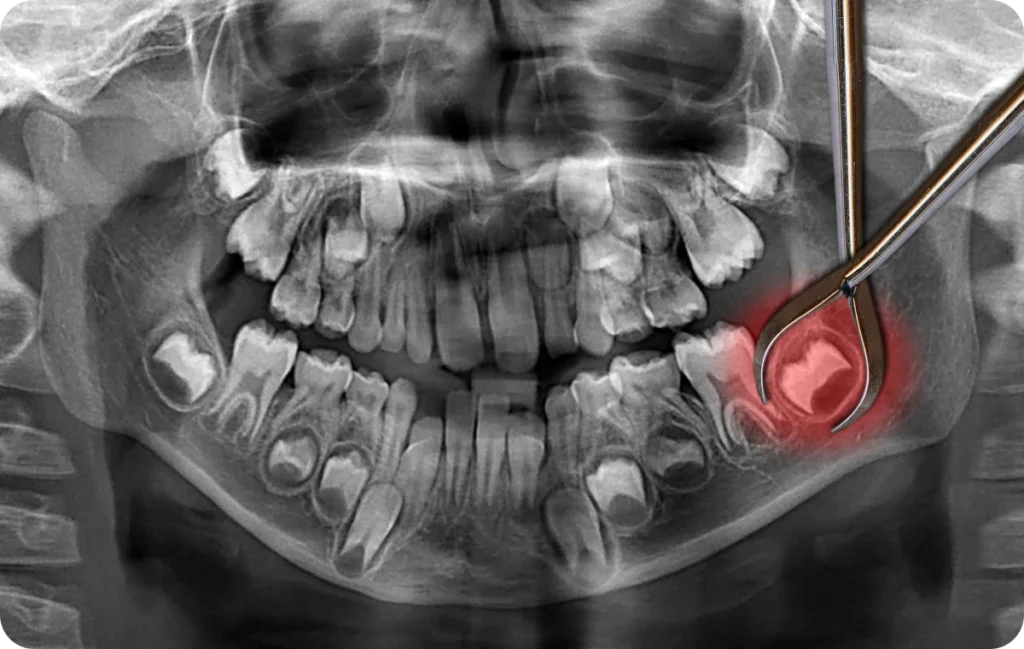

Lors d’une consultation, le praticien examine la bouche et propose généralement une radiographie panoramique. Cet examen permet de visualiser la position exacte des dents de sagesse, leur orientation et leur relation avec les structures voisines (racines des molaires, nerfs, sinus).

Un suivi régulier, même sans symptôme, permet de prévenir des complications plus difficiles à traiter ultérieurement.

Un contrôle annuel chez le chirurgien-dentiste permet d’évaluer la position des dents de sagesse. La radiographie panoramique reste l’examen de référence pour anticiper d’éventuelles complications.